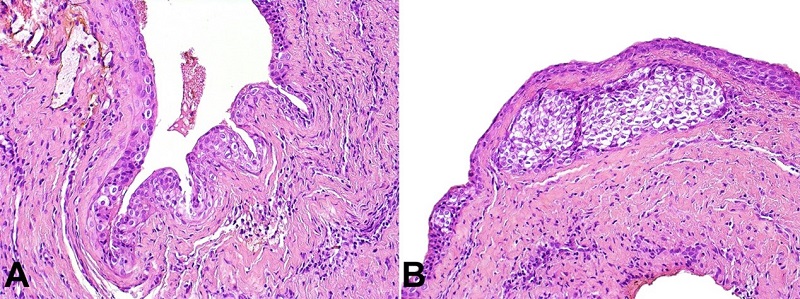

A surgical excision was performed, and histopathological findings revealed multiple cystic cavities lined by squamous epithelium of varying thickness with focal areas of nodular thickenings. The presence of clusters of cells with clear cytoplasm within epithelial thickenings was observed (Figure 2). PAS staining was negative in the clear cells. The diagnosis of the GCA was established. No signs or symptoms of lesion recurrence were observed at 1-year follow-up.

Histologic features of GCA include a non-inflammatory fibrous capsule lined by a non-keratinized thin epithelium, eventually with areas of thickening.6,10 It may also show remnants of glycogen-rich clear cells from the dental lamina, cystic enlargement, and degeneration with the formation of microcysts.2